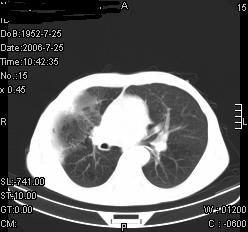

患者,男,54岁,咳嗦,咳痰20天。抗炎治疗2周。现esr76mm/h,目前患者症状明显好转,但发现两次ct片未见明显变化。两次分别做与7.25、7.31。第一次诊断右肺上叶炎症累计胸膜。大家看,从影像上内排除结核吗?

结核的可能性非常大,右上肺病变应该考虑干酪性肺炎。理由:

1.纵隔内多发淋巴结肿大。

2.esr76mm/h。

3.虽经抗炎治疗肺窗病灶有所吸收、减小,但纵隔窗病灶形态、密度、范围无明显变化。如果是单纯的大叶性肺炎,“抗炎治疗2周,目前患者症状明显好转”病灶应该基本消散了,至少也处于吸收消散期,密度变淡、范围变小。同时本病例所示其内的密度不均匀,见多发大小不一空洞样影也不符合大叶性肺炎吸收消散期表现。

病灶特点:片状 索条 结节混杂影,部分融合,密度不均,广泛累及相应胸膜.

临床治疗;二周未吸收.但症状好转.

多考虑:肺结核.